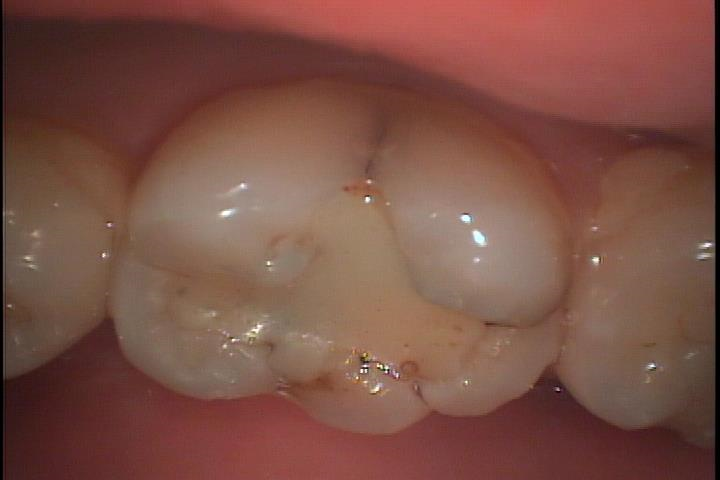

症例です

歯を上から眺めて見ます。

少し角度を変えて側面から見るとクラックに色素が沈着し黒くなっているのがわかります。虫歯になっている可能性が高いです。

歯の表面はエナメル質という硬い構造に守られていますが、クラックが入るとそこから虫歯が進行します。